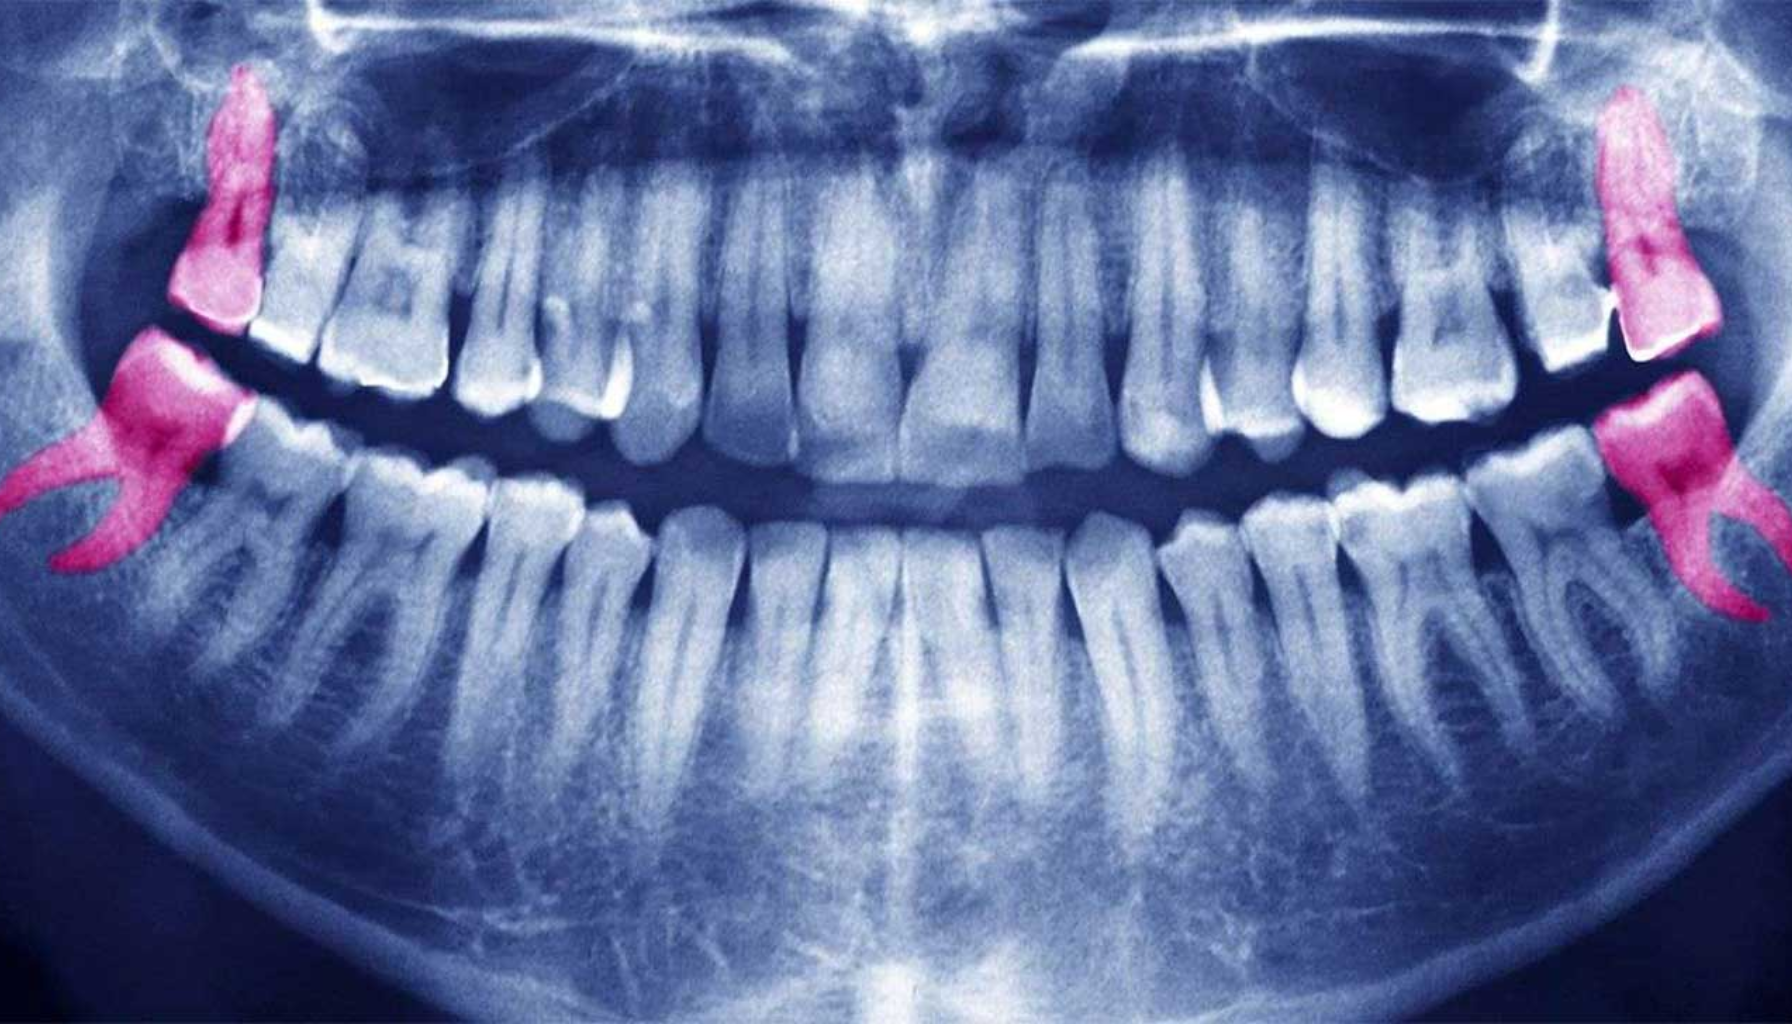

En retinert visdomstann er en tann som ikke klarer å bryte gjennom tannkjøttet og komme helt frem i munnen. Dette skjer vanligvis fordi det ikke er nok plass i kjeven, eller fordi tannen vokser i feil vinkel. Retinerte visdomstenner er vanligst hos personer mellom 17 og 25 år, når visdomstennene normalt kommer. De kan være helt skjult i benet eller delvis synlige under tannkjøttet.

En røntgenundersøkelse hos tannlege avslører om tannen er retinert og hvilken retning den vokser i. Dette gir grunnlag for videre vurdering. Selv om det er en vanlig tilstand, bør den følges nøye opp for å unngå smerter og komplikasjoner.